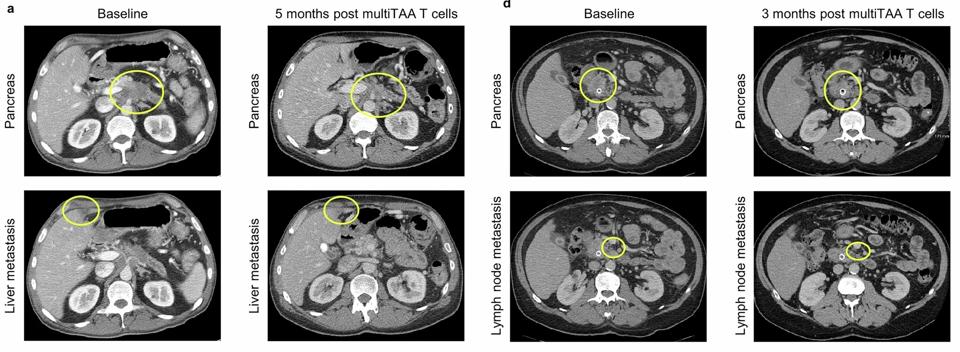

Pendekatan inovatif dengan CAR T multi-antigen yang menargetkan lima penanda berbeda pada sel kanker pankreas kini sedang diuji dalam uji klinis. Ini memungkinkan sel imun untuk mengenali lebih dari satu target sehingga kemungkinan besar terapi ini efektif walaupun kanker berusaha menyembunyikan diri dengan mengubah sebagian penandanya.

Hasil awal dari uji klinis menunjukkan terapi ini aman dan dapat memperpanjang masa hidup pasien dibandingkan dengan pengobatan standar saat ini. Terapi ini juga sedang dikombinasikan dengan pengobatan lain untuk meningkatkan efektivitasnya. Jika berhasil, pendekatan ini dapat menjadi pijakan penting dalam pengembangan pengobatan kanker pankreas di masa depan.